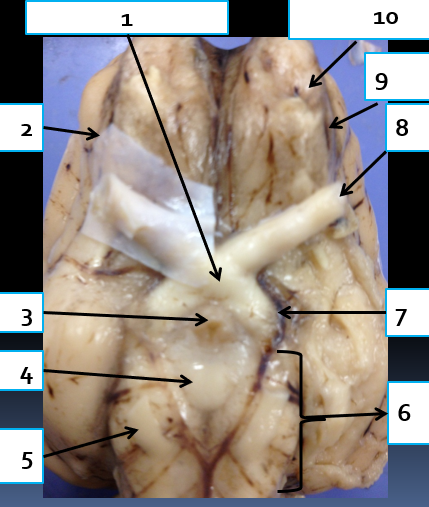

1

infundibulum, connects hypothalamus to pituitary gland

2

oculomotor nerve, CN3, eye muscle control

3

cerebral peduncle, connects cerebrum to pons

4

trigeminal nerve, CN5, motor control of jaw muscles

5

abducens nerve, CN6, eye muscle control

6

spinal cord, reflex area

7

medulla oblongata, controls vital autonomic functions like heart rate

8

9

pons, connects brain with lower CNS centers

10

mammillary body, relay station for olfaction

11

optic tract, carries visual information from optic chiasma to visual cortex

12

optic chiasma, area where medial portion of optic nerves cross

13

optic nerve, CN2, vision

14

olfactory bulb, houses synpases of olfactory nerve fibers, CN1, olfaction